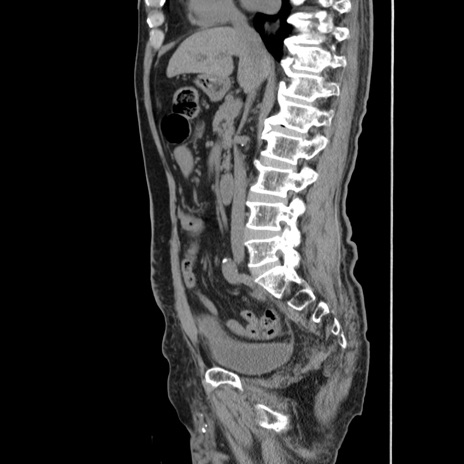

症例24(矢状断像)

【症例】80歳代男性

【主訴】左側腹部痛、嘔吐

【現病歴】本日早朝より左腹部に痛みあり。昼頃嘔吐認めたため、救急要請。

【既往歴】直腸癌(Mile手術)、胆摘

【身体所見】意識清明、BT 35.9℃、BP 221/93mmHg、SpO2 97%(RA) 、腹部:左ストーマ周囲に限局性の腹部膨隆あり。 膨隆部自発痛・圧痛あり・軟。

【データ】WBC 7700、CRP 0.09